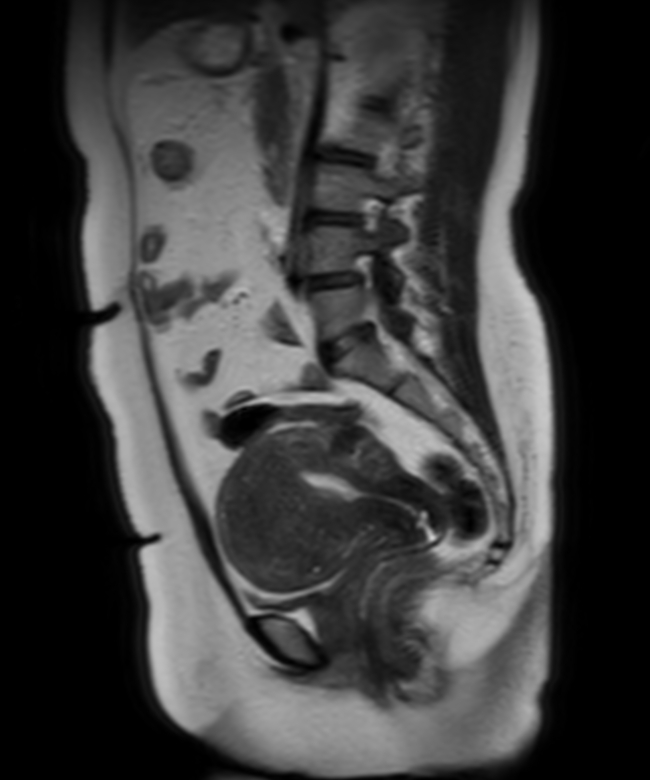

Sagittal 3D PelvisVIEW